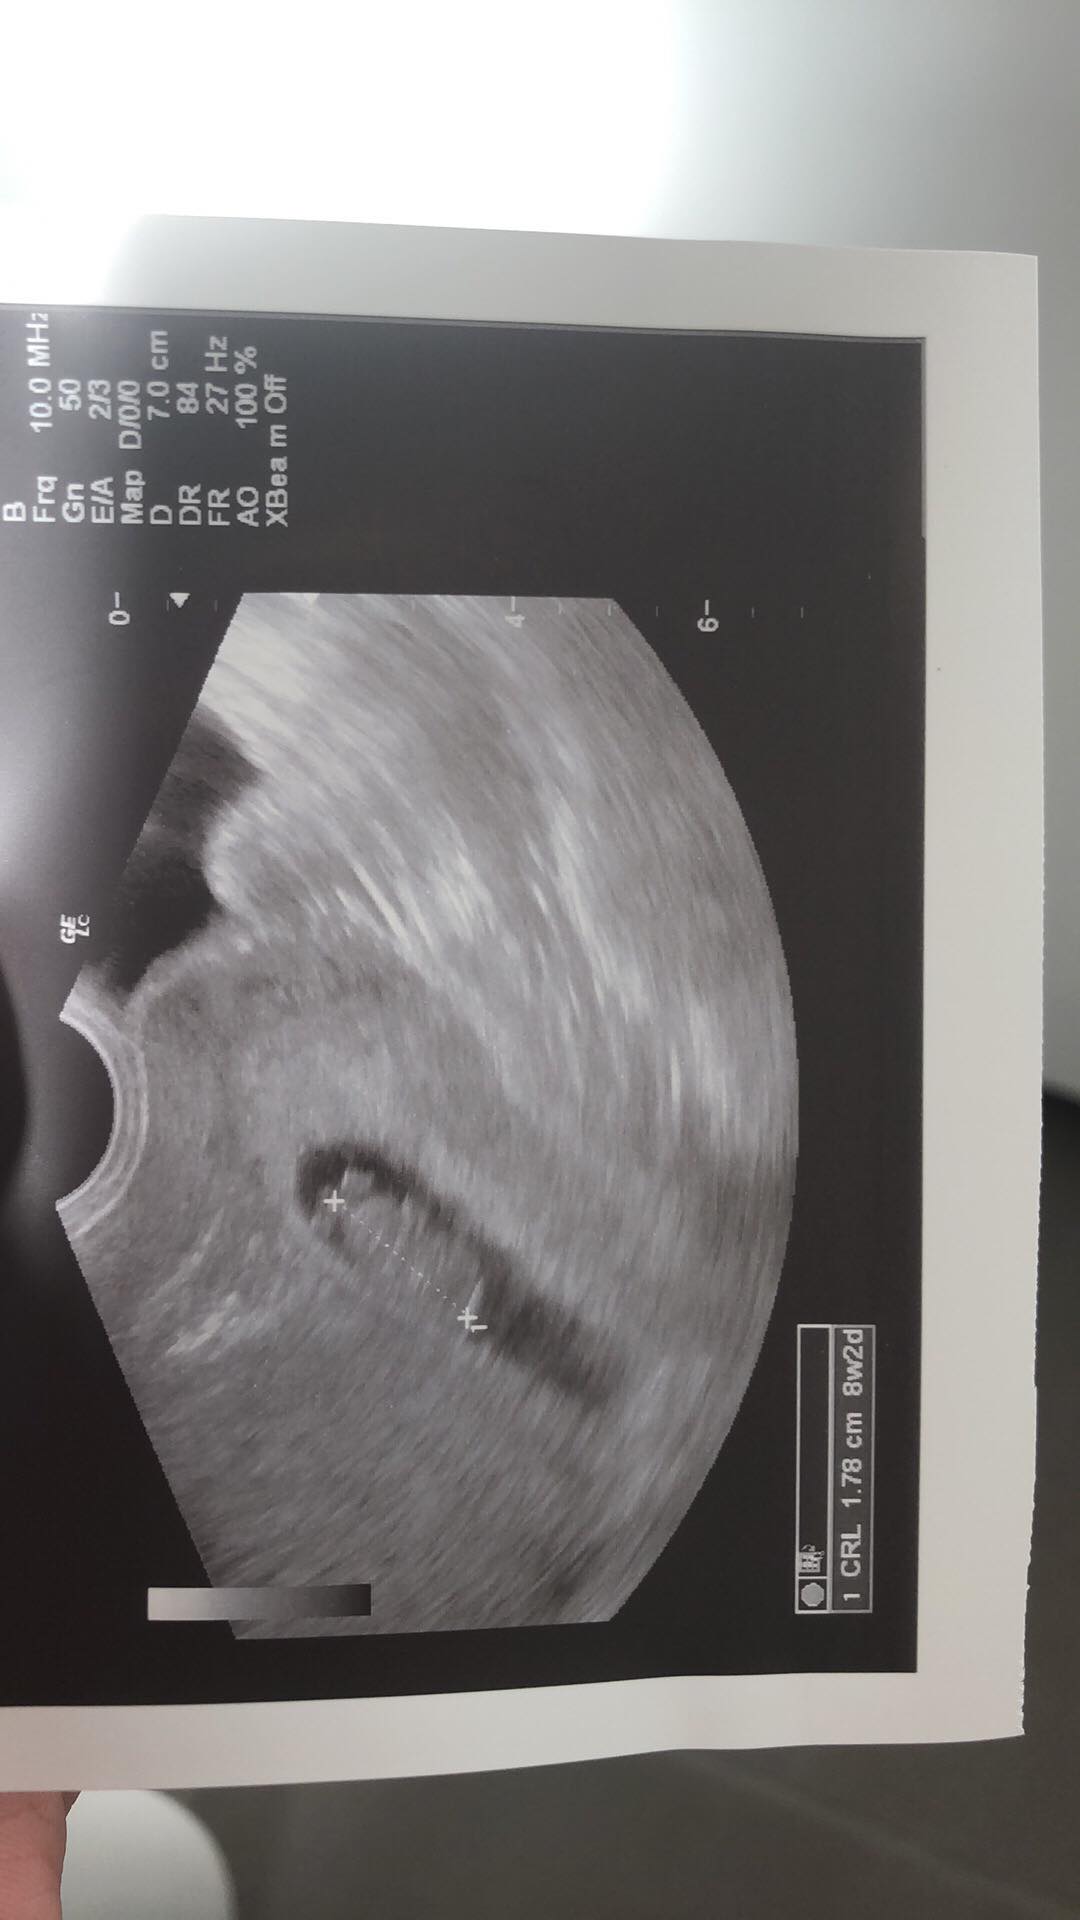

Witam sie Dziewczyny, dawno, dawno nie pisalam, ale wracam z wiescia, jestem w 8tc

dzisiaj potwierdzone u lekarza, serduszko bije, 180/min, przyrosty bety bardzo wysokie ponad 370% pierwszy, jestem bardzo szczesliwa, ze wreszcie sie udalo